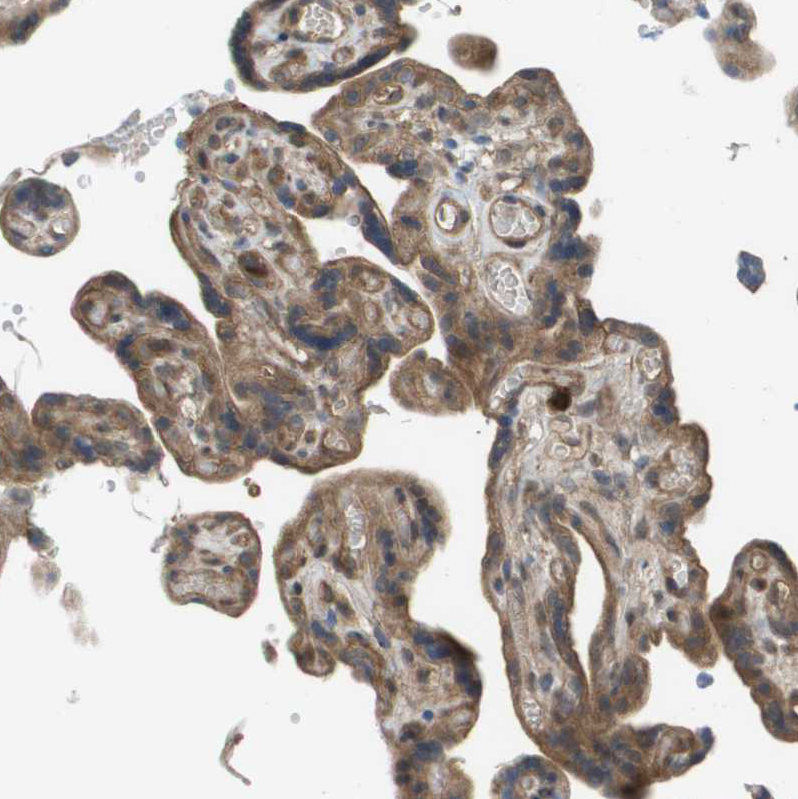

Immunohistochemical staining of human endometrium shows strong cytoplasmic positivity in glandular cells.